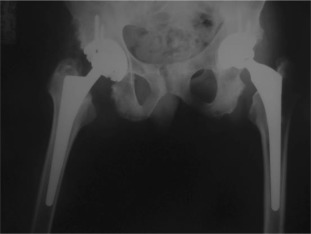

There were 61 patients (50 male, 11 female) with 105 affected hips (72% bilateral, 28% unilateral). The average patient age at surgery was 41.3 ± 10.2 years old. The age of patients at THA was as follows: <30 years for 14 patients (23 hips), 31–50 years for 41 patients (73 hips) and >50 years for 6 patients (9 hips) (Graph 1 ). The younger age at diagnosis (<30 years old) of AS was correlated with younger age at THA (p < 0.05). Bone ankylosis was detected in 37 (35%) and acetabular protrusion was noticed in 18 (17%) hips in pre-operative radiographs (Fig. 1 , Fig. 2 , Fig. 3 ; Fig. 4 ) (Table 1 ). The mean pre-operative flexion contracture was 20.3°±21.8°. In patients without ankylosis, the mean total hip range of motion (ROM) was 67.8°±25.7°.

Fig. 2. Four years after bilateral simultaneous THA. |

Fig. 4. Six years after right side, five years after left side THA. |